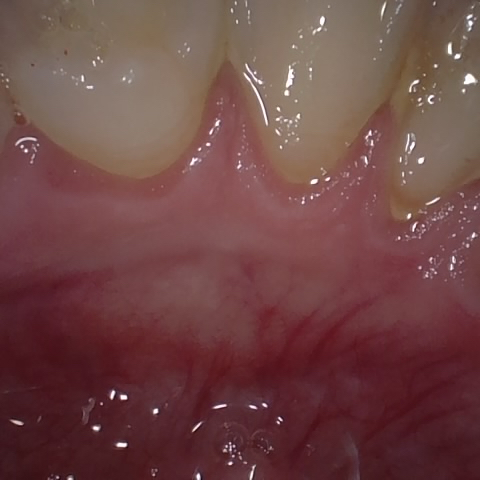

Annotated as "Good"